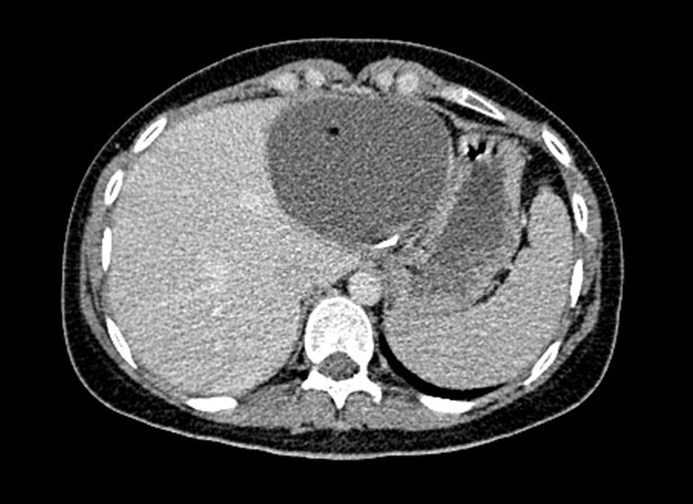

Typical image of cysticerci. CT scan showing many active cysts